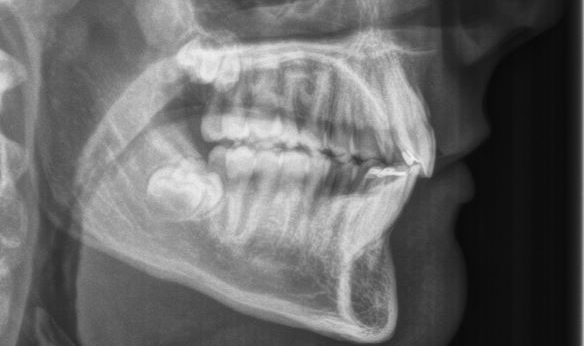

Jaw Surgery